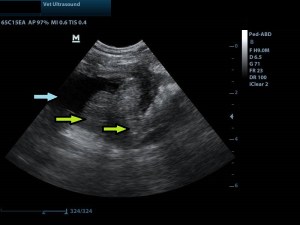

Ευρήματα: Στον υπέρηχο κοιλίας βρέθηκε νεοπλασία στο τρίγωνο της ουροδόχου κύστης το οποίο φαινόταν να διηθεί τους γύρω ιστούς. Το νεόπλασμα εμπόδιζε την έξοδο των ούρων μέσω του αριστερού ουρητήρα όπου είχε προκαλέσει υδρονέφρωση του σύστοιχου νεφρού. Ο δεξιός ουρητήρας και η νεφρική πύελος ήταν διατεταμένοι 7 mm (φυσιολογικό μέγεθος < 3 mm), χωρίς όμως να έχει επηρεαστεί η δομή του δεξιού νεφρού.

μπλε βέλος: υδρονέφρωση του αριστερού νεφρού

αριστερά της εικόνας ο προσανατολισμός του κέρσορα είναι κεφαλικά (ο θόλος της ουροδόχου κύστης και ουραία το νεόπλασμα)

μπλε βέλος: κοιλότητα της ουροδόχου κύστης γεμάτη με ούρα (μαύρο)

κίτρινο βέλος: η μάζα η οποία διηθεί και το τοίχωμα της ουροδόχου κύστης